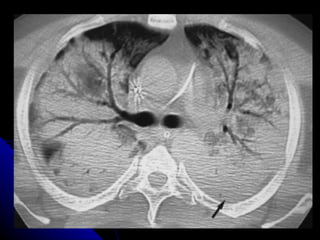

RADIOLOGIA Los infiltrados pueden ser muy pequeños y difíciles de apreciar especialmente en radiografías portátiles. La pausa inspiratoria es prácticamente imposible cuando el paciente se encuentra en ventilación mecánica haciéndolas menos específicas para el diagnóstico. La Tomografía Axial del tórax puede diagnosticar hasta en un 26% más, infiltrados pulmonares a más de definirlos más exactamente que la placa simple del tórax

RADIOLOGIA Los infiltradospueden ser muy pequeños y difíciles de apreciar especialmente en radiografías portátiles. La pausa inspiratoria es prácticamente imposible cuando el paciente se encuentra en ventilación mecánica haciéndolas menos específicas para el diagnóstico. La Tomografía Axial del tórax puede diagnosticar hasta en un 26% más, infiltrados pulmonares a más de definirlos más exactamente que la placa simple del tórax